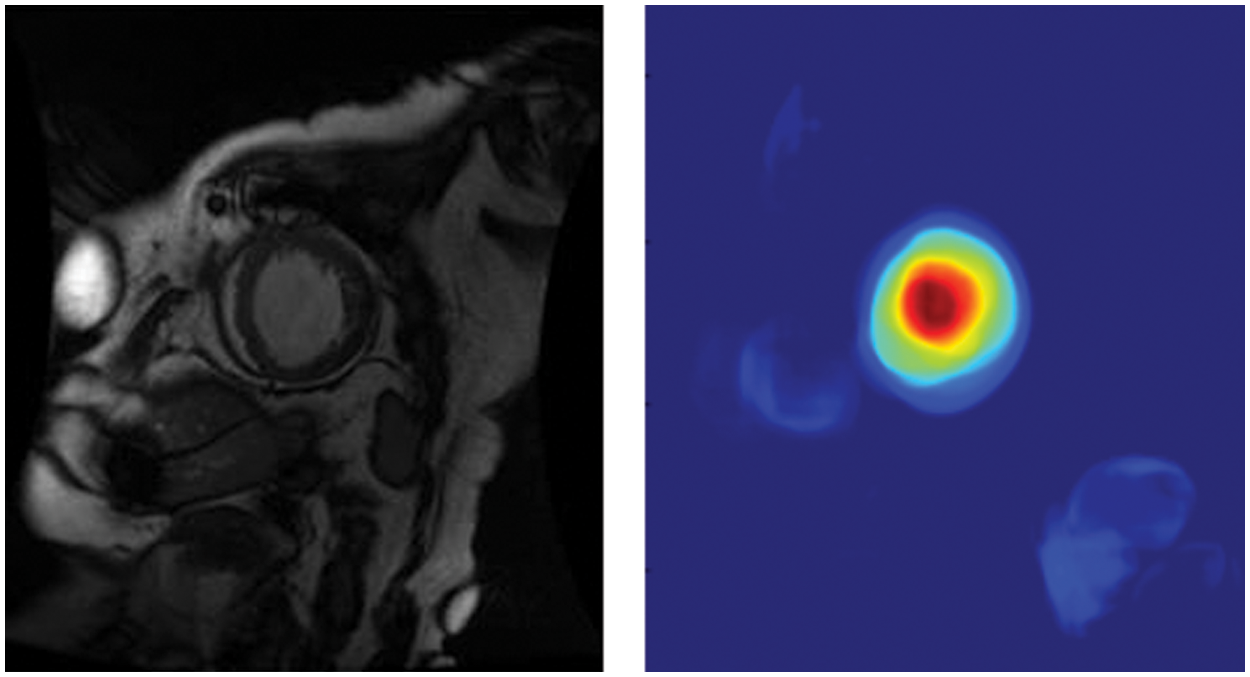

We enhanced NVIDIA DIGITS by employing class activation maps (CAM) [26] to generate visual interpretations of CNN predictions. CAM uses the GAP layer in the CNN to generate a map highlighting which parts of an image the network uses in relation to a specific class label. According to Fig. 6, we can see which portions of the image are important in the image classification. We could use the GAP layer and the heat map to simultaneously determine where objects are in the image. The red portion of the figure indicates that the model has been placed at the center of the left ventricle, and the cyan edge outlines the left ventricle’s boundary. It assists doctors in understanding how the model recognizes the left ventricle and model developers in determining whether the model is accurate.

Figure 6: Global average pooling layer visualization